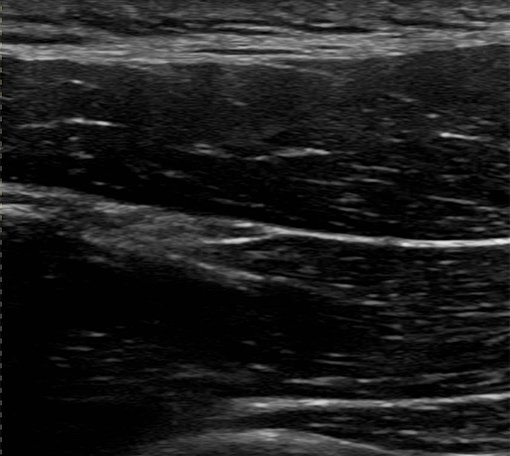

腰痛への超音波エコーガイド下鍼

腰部の筋・神経の状態をリアルタイムで確認し、原因に直接アプローチ。ぎっくり腰や慢性腰痛にも安全に施術します。